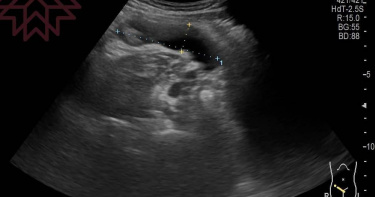

40歲男上腹劇痛冒冷汗 膽腫成「士林大香腸」嚇壞醫

一名40歲有膽結石的男子,近日吃了消夜後腹痛冒冷汗,急診後隔天狀況沒改善,就醫才發現膽腫如「士林大香腸」,需要緊急進行手術。開業胰臟醫師林相宏在臉書分享,壞死性膽囊炎等不得,而有膽結石患者要小心,一名40歲男性健檢發現膽結石,平常會胃痛,也曾掛過急診,但都是打針吃藥就沒事,最近男患者吃了消夜,上腹部劇烈疼痛,痛到冒冷汗,「尤其是吃了點東西又會更加疼痛,小便顏色也變得比較深色,半夜去了急診,打個針之後就回家觀察。狀況似乎沒有好轉。」男子膽腫成「士林大香腸」。(圖/翻攝《胰臟醫師 林相宏 禾馨民權內科診所》臉書)林相宏幫男子照超音波後嚇壞,「整個膽腫得像士林大香腸一樣,而且膽囊壁有點不規則,膽囊周圍水腫,像是傷口化膿那樣,高度懷疑是一種膽囊炎的急症,壞死性膽囊炎,趕緊轉診手術。」壞死性膽囊炎死亡率比一般膽囊炎高,「原本應該顏色紅潤的膽囊,已經整個壞死翻黑,而且有些地方已經接近膽囊破裂很像是快破的水球,好險緊急手術,不然一旦膽囊破裂,就變成嚴重腹膜炎外加敗血症,後果以及後遺症不堪設想。」林相宏表示,9成至9成5的膽囊炎,是膽結石導致,而膽囊腫到一定程度,就會引起血管缺血,「如果常常喜歡應酬,加上喜歡吃高油脂的食物,像是速食、炸雞等,都要很小心,年紀大(>50歲)、男性、糖尿病、心血管疾病族群是高風險族群,以上這些族群對疼痛的感受性比較低。」林相宏強調,一開始缺血因神經不敏感,所以不會感覺很痛,因此會延誤就醫,「等到後續膽囊壞死甚至破裂,才開始有嚴重的腹痛、發燒等,所以有膽結石族群,有上腹部疼痛,最好即早就醫接受超音波檢查。」